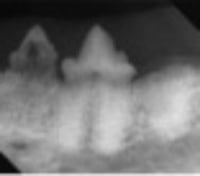

Resorptive lesions

Source: Center For Veterinary Dentistry &

Oral Surgery